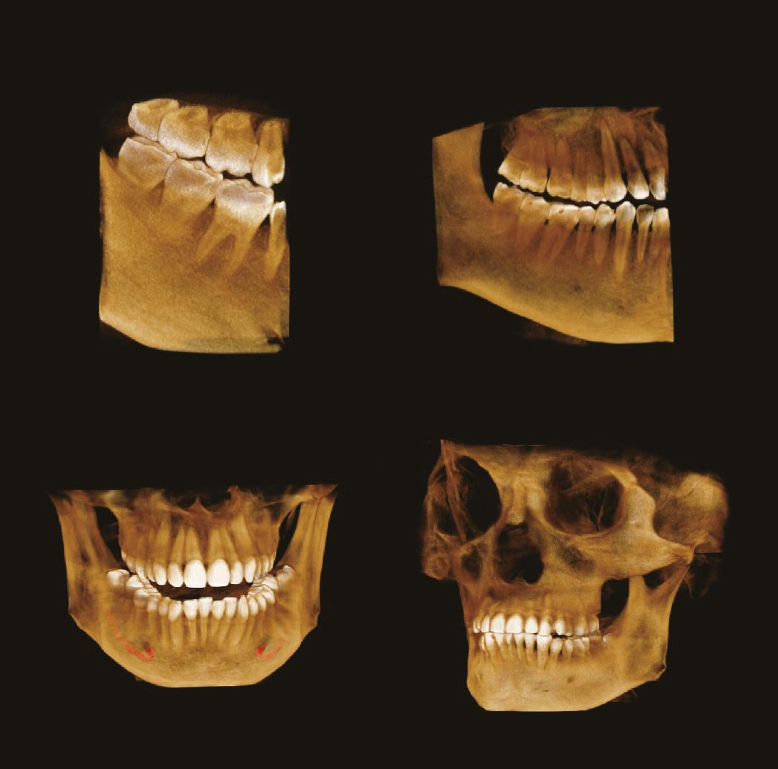

Устройство оснащено множеством функций, позволяющих проводить качественное и всестороннее обследование. Специально для стоматологов томограф поддерживает эндодонтический режим. Эта функция позволяет делать снимки в разрешении 70 мкм. Снимок получается размером 3,5×4 см. Высокую чувствительность на снимках обеспечивают сенсоры из теллурида кадмия.

Устройство оснащено множеством функций, позволяющих проводить качественное и всестороннее обследование. Специально для стоматологов томограф поддерживает эндодонтический режим. Эта функция позволяет делать снимки в разрешении 70 мкм. Снимок получается размером 3,5×4 см. Высокую чувствительность на снимках обеспечивают сенсоры из теллурида кадмия.